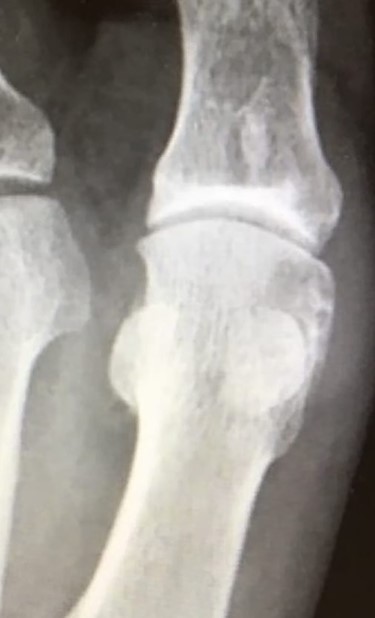

Postoperatively touch weight-bearing was allowed for 6 weeks with gradual full weight-bearing after 6 weeks. At 12 months follow-up, the range of motion of the 1st MTP joint was improved (50° of dorsiflexion and 30° of plantar flexion). An X-ray was taken, showing the restoration of the joint surface (Fig. 6).

Anteroposterior X-ray view of the left foot at 12 months follow-up showing a good-restoring articular cartilage and joint regularity.